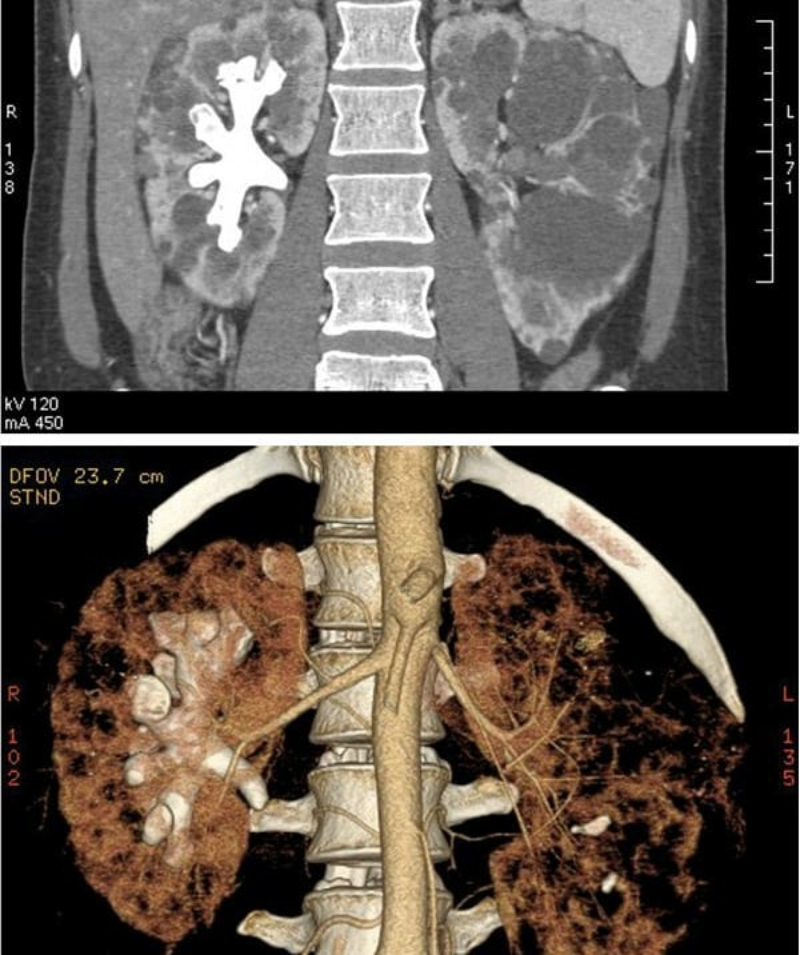

Cuatro imágenes de cálculos renales coraliformes.